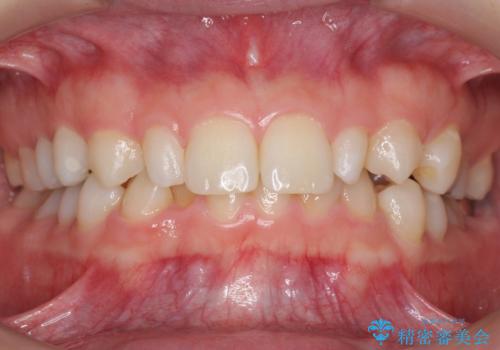

- 37万円(左上4:e-max クラウン 7万円x4、仮歯 1万円x4 右上2ファイバーコア:2万円x1 プレミアムナイトガード 3万円) 矯正治療は別費用は治療当時の料金となります

下の前歯との距離(クリアランス)が大きくは取れなかったため、ジルコニアクラウンではなくe-maxクラウンにしました。

また、歯ぎしりでセラミックがかけるのを防ぐために、就寝時にはナイトガードを装着してもらっています。